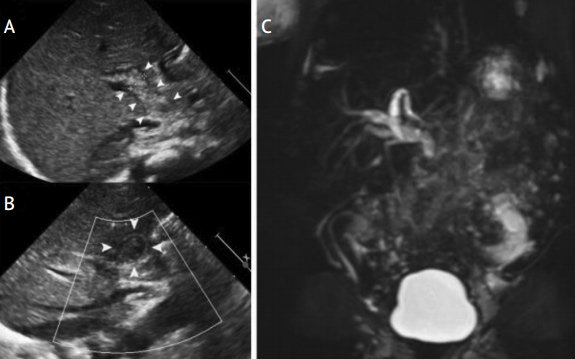

В диагностически трудных случаях для подтверждения синдрома сгущения желчи проводится магнитнорезонансная холангиография [1]. В пользу синдрома сгущения желчи свидетельствуют маленький желчный пузырь, диффузная дилатация интрапеченочных и экстрапеченочных желчных протоков, резкое сужение общего желчного протока после зоны дилатации (рис. 3).

Рисунок 3. Синдром сгущения желчи

Figure 3. Bile thickening syndrome

УЗИ (А, В): умеренная дилатация интрапеченочных желчных протоков, дилатированный общий желчный проток, заполненный неоднородной эхогенной массой. Магнитно-резонансная холангиография (С): маленький желчный пузырь, умеренная дилатация интра- и экстрапеченочных желчных протоков, внезапный обрыв общего желчного протока, отсутствие пассажа желчи в двенадцатиперстную кишку [1].